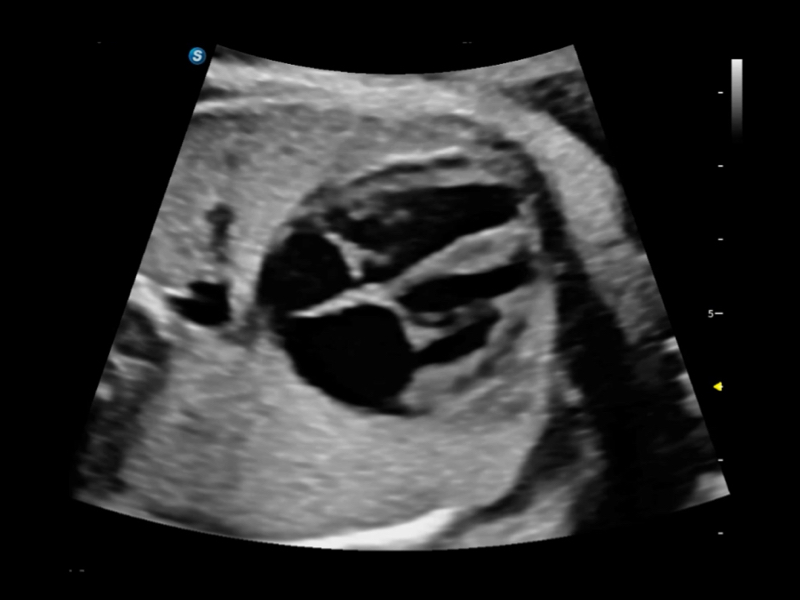

提供解剖示意图、标准超声图像、扫查手法图和操作者实时检查图像,指导操作者进行标准切面的正确扫查。